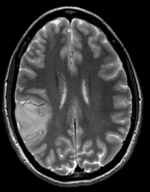

this is the fixed reference image. All images are aligned into this space lleft this is the T2 reference image, serves as target to the DTI baseline, but is itself aligned to the SPGR lleft this is the DTI tensor image, in the same orientation as the DTI Baseline

fixed image 1

T2

This is a classic case of a multi-sequence MRI exam we wish to spatially align to the anatomical reference scan (T1-SPGR). The scan of interest is the DTI image to be aligned for surgical planning/reference. Unlike Case 27 this one does contain both a T1 and a T2 image. The T2 image being closer in contrast to the DWI/DTI baseline, it makes for the better registration reference. However the T1 contains the tissue contrast of interest.

Approach: we can use either T1 or T2 as the spatial reference. Ultimately we seek to overlay the DTI information onto the T1 image. But the T2 makes for a better registration reference because it matches better the DTI baseline contrast. Hence we will use the T2 as the reference and align the T1 to the T2 in a separate registration step. The typical DTI challenges are present here also: